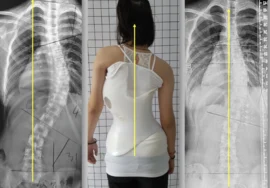

يُعد اعوجاج العمود الفقري (الجنف) من الحالات الشائعة التي تصيب الأطفال والمراهقين خلال مراحل النمو، ويمكن أن تستمر أو تظهر في مرحلة البلوغ. ومن بين العلاجات غير الجراحية الفعالة التي تُستخدم لتقويم العمود الفقري وتقليل تطور الانحناء، يبرز الحزام الطبي أو الجبيرة القطنية كأحد الحلول الأساسية، لكن يبقى السؤال: متى يجب البدء في استخدام الحزام؟ ومتى يكون غير فعال؟

ما هو الهدف من استخدام حزام اعوجاج العمود الفقري؟

الهدف الرئيسي من استخدام الحزام الطبي لعلاج الجنف هو:

إبطاء أو منع تفاقم الانحناء أثناء مرحلة النمو.

- تحسين استقامه العمود الفقري

تقليل الحاجة للتدخل الجراحي.

تحسين الوضعية العامة للجسم.

تخفيف الأعراض المرتبطة بالجنف مثل الألم أو التعب.

متى يبدأ استخدام حزام اعوجاج العمود الفقري؟

توصي الجمعية الدولية للجنف باستخدام الحزام الطبي في الحالات التالية:

انحناء يتراوح بين 25° و45° لدى المرضى الذين لا يزالون في مرحلة النمو.

انحناء أقل من 25° لكنه يتطور بمعدل يزيد عن 5° خلال ستة أشهر.

حالات الجنف بين 20° و25° عند وجود علامات واضحة لعدم اكتمال النضج الهيكلي (مثل Risser 0 أو Tanner 1-2).

وفي هذه المراحل، يُعتبر الحزام خيارًا فعالًا للحفاظ على استقامة العمود الفقري وتفادي تدهور الحالة.